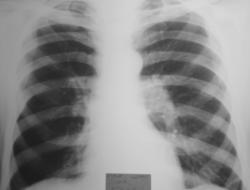

24.10.08 г. пациенту был сделан обзорный снимок органов грудной полости, на котором вызвало смущение расширение левого корня и некоторая не структурность правого корня.